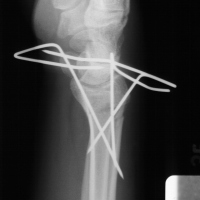

| Case 6 Extraarticular distal radius fracture with angulation and dorsal comminution. |

| Attempts at

closed reduction alone were unsuccessful. |

| Freer elevator

introduced percutaneously as a reduction aid. |

| Percutaneous

fracture stabilization with three pins via the

dorsal radial tubercle, radial styloid and FCR

portals. |

| Pins were left

protruding and bent to overlap. |

| Thermoplastic-pin

construct at 6 weeks, immediately prior to removal. |

| Late result. |